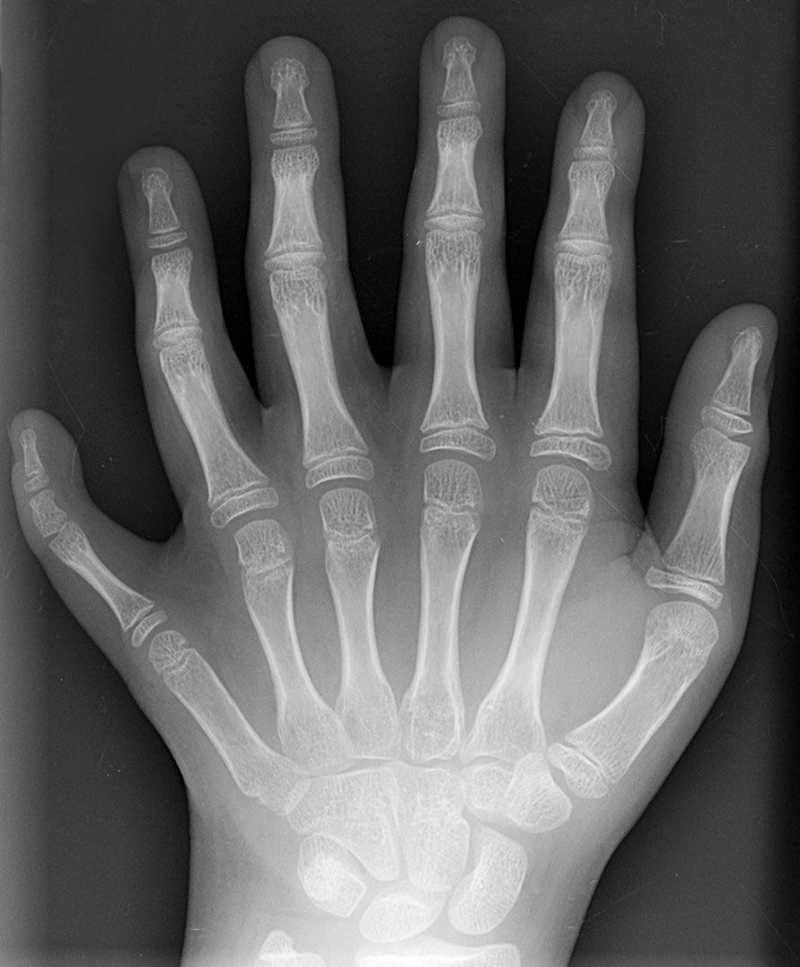

6. Ολιγοδακτυλία- λιγότερα δάχτυλα.

Η ολιγοδακτυλία είναι μια σπάνια γενετική διαταραχή που οδηγεί ένα άτομο να γεννιέται με λιγότερα από πέντε δάχτυλα στα χέρια ή στα πόδια. Αν και τα δάχτυλα λειτουργούν σε πολλές περιπτώσεις, αυτό εξαρτάται επίσης από τη σοβαρότητα της διαταραχής.

7. Πολυδακτυλία- επιπλέον δάχτυλα.

Σε αντίθεση με την ολιγοδακτυλία, η πολυδακτυλία αναφέρεται σε ένα άτομο που γεννιέται με επιπλέον δάχτυλα στα χέρια ή στα πόδια. Επίσης, είναι μια πάθηση κληρονομική όπως αυτή της ολιγοδακτυλίας.